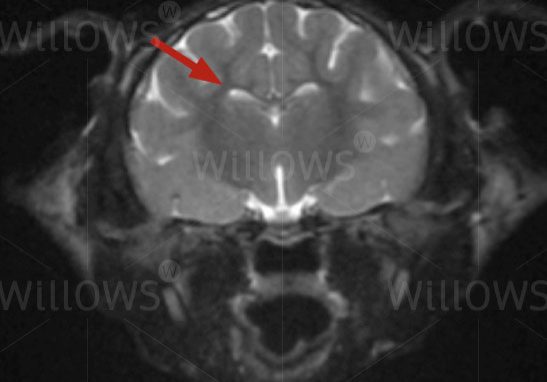

MRI scan of the brain (arrow) – this view is a cross-section seen from the back